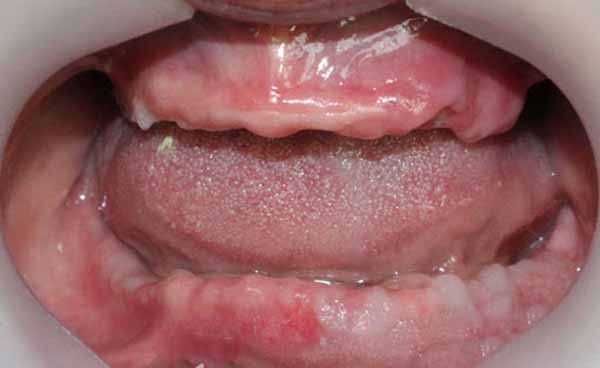

- Tiêu xương hàm trên nặng, đặc biệt vùng tiền đình và xoang hàm, không đủ xương để đặt implant truyền thống

5. Theo dõi & bảo dưỡng định kỳ

- Tái khám kiểm tra:

- Mức độ tích hợp implant

- Tình trạng mô mềm quanh implant